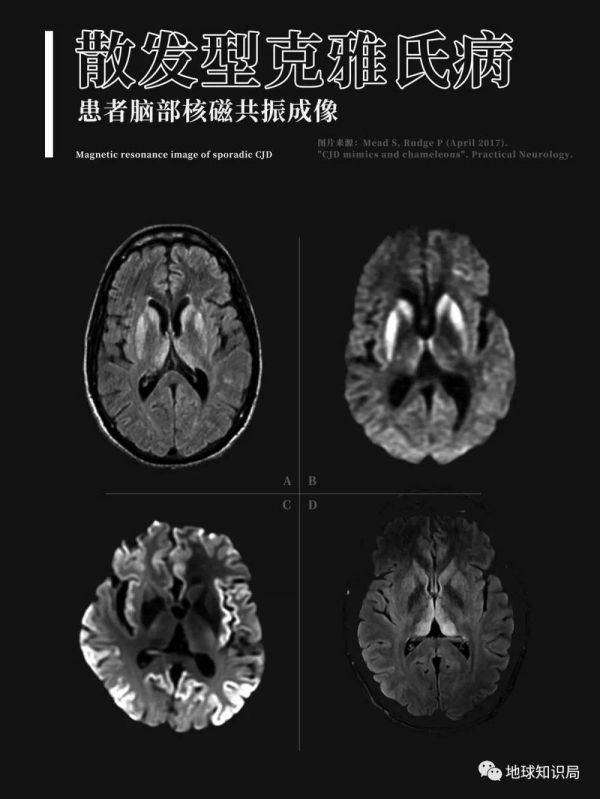

这种早在20世纪初就被明确记录的疾病通常有如下表现:起病缓慢,开始时出现记忆力减退及头痛,之后迅速判断力下降、人格障碍,定向力障碍,最终患者完全痴呆,并有共济失调和四肢肌肉的震颤抽搐。

无论是羊瘙痒症,还是库鲁病、克雅氏病,解剖提示这些患病个体大脑出现了大量异常的空洞,所有这一切都说明这些疾病是由同一种病原体造成;同时还表明,存在一种未知的病原体,它不是细菌,也不是病毒,甚至可能颠覆以往对生命的定义。

大脑萎缩,空洞明显